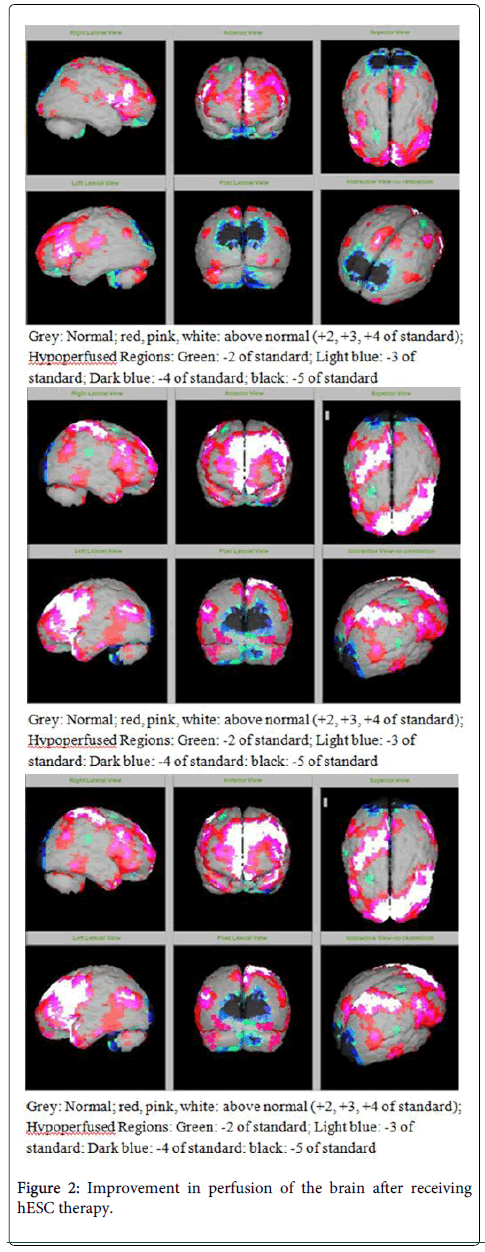

該患者的SPECT掃描如圖1和2所示。

圖2:接受hESC治療后大腦灌注得到改善

SPECT掃描

在研究開始和結束時,23名患者接受了SPECT掃描。在枕葉或額葉或雙葉中觀察到灌注不足。23例接受SPECT掃描的患者中,5例患者表現為枕葉灌注不足,7例患者表現為額葉灌注不足,11例患者表現為枕葉和額葉灌注不足。

總體而言,治療結束時,2名患者的灌注正常,18名患者(12名男性和6名女性患者)顯示灌注顯著改善(>60%),3名患者顯示灌注中度改善(30-60%)。大多數在接受hESC治療前額葉和枕葉嚴重低灌注的患者在接受 hESC 治療后情況有所改善。23名可獲得SPECT掃描報告的患者的GMFCS評分在hESC治療后有所改善(表2)。

眾所周知,神經干細胞可以通過重新填充受損區域并防止細胞進一步退化來恢復正常視力。hESC通過增殖成相似的細胞類型來啟動受損細胞的再生。在本研究中觀察到灌注改善,這反映在SPECT掃描中。詹森等人研究顯示,一名5歲腦癱患者在接受臍帶血干細胞治療2個月后視力有所改善。